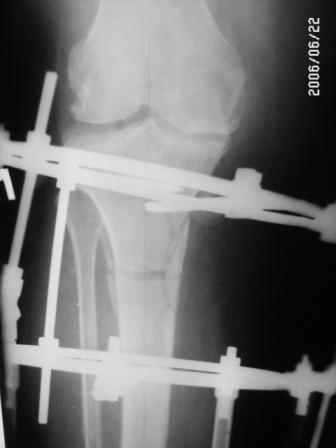

Глядя на снимки, кроме оперативного лечения в голову ничего не приходит. Хотя бы корригирующая кортикотомия б/б кости с минимальной внешней фиксацией. Высылаю пример.

На последнем фото внешний вид больной на завершающем этапе лечения (30 сутки) с трансформацией АВФ из гибридного в стержневой. Боль уходит сразу после операции. При данной Р-картине консервативно показано применение только обезболивающих препаратов - трамадол до 3 мес. по 100-200 мг в сутки, возможно внутрисуставное введение морфина 1,0 мл. При скрыто протекающем синовиите добавляются НПВС. Кроме того, должна помочь остеорефлексотерапия - в/костной иглой пункция проксимального метафиза б/б кости с введением 1,0-0,5 мл. физ.р-ра или новокаина. Возможе и вариант расширенного вмешательства по Беку: узким долотом через кожный разрез в 3-4 мм делается «прокол» кортикального слоя и маятникообразными движениями разрушается костный мозг. Боль проходит практически всегда и надолго.